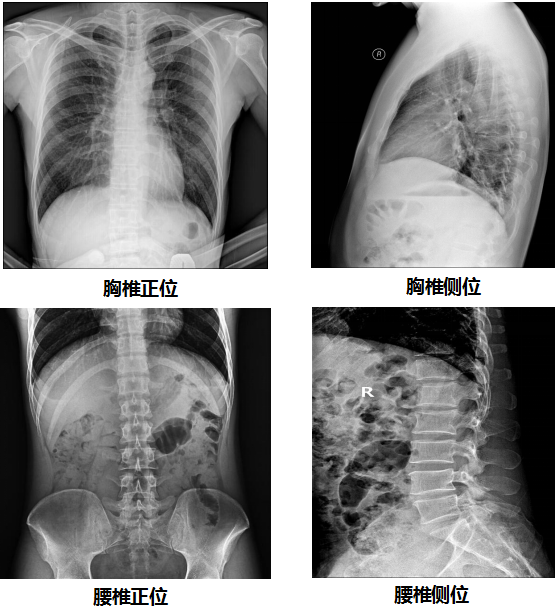

【PLD7300系列双立柱DR临床图像】